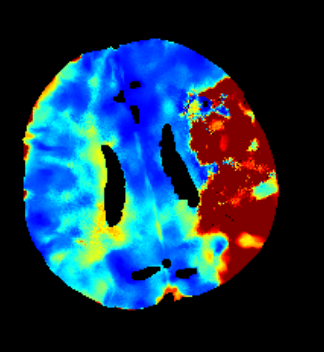

Furthermore mRay is capable of performing image processing tasks such as finding, visualizing and quantifying anomalies in tissue. In particular the image analysis module mRay VEOcore may be used to perform an automated processing of brain images from imaging modalities such as CT, CT-Perfusion, or MRI including a Diffusion Weighted Imaging (DWI) Module. As a result, changes in contrast over time are visualized as colored perfusion maps, including flow related parameters and tissue blood volume quantification.

The perfusion analysis of brain imaging data visualizes and quantifies tissue that is less supplied with blood (penumbra), oxygen deprived tissue caused by obstructed blood flow (core tissue) and the mismatch ratio between the two. The calculated values can be used to support decision making based on an assessment of the extent of tissue damage.

16.1. Overview

VEOcore is a fully automated image processing tool to calculate quantitative measures of affected brain tissue and healthy tissue. Therefore, this manual covers the instructions on how to interpret the results. It’s an extension the mRay Server application and the results can be viewed inside the mRay Client. Furthermore processed results can be automatically forwarded to the PACS.